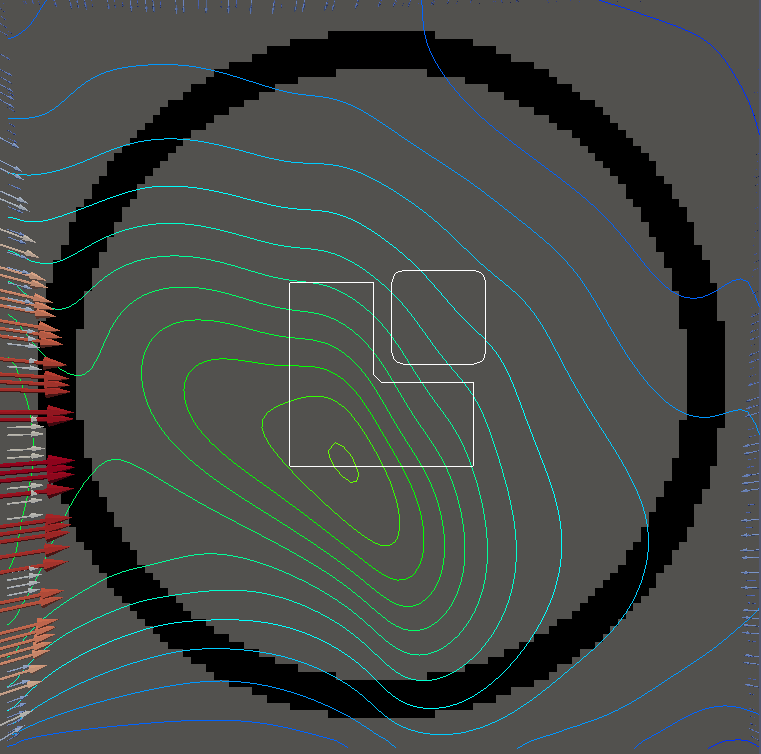

For testing, we use three tumor/risk region regions similar to those in [13]. Specifically, we define the regions in Table 3 and are shown in Figure 1; the void region is shown in black and the tumor and risk regions are traced in white. In the basic target case, seen in Figure 1(a), the tumor region is a box, as is the risk region. The second, intermediate target case, seen in Figure 1(b), involves an L-shaped tumor around a box-shaped risk region. Finally, the complex target case in Figure 1(c) involves a C-shaped tumor around a risk region.

We will solve both and for each geometry seen in Figure 1. For for each example, we set on and elsewhere, corresponding to an average (over time) dose of and

Figure 2 shows the optimal boundary source term for both and The vectors shown on the boundary are the time-integrated values of normalized and then scaled by In Figures 2(a), 2(c), and 2(e) (corresponding to ), the isolines are spaced at intervals of the maximum of the desired dose (here, 5). In the intermediate and tracking cases, we see that relatively low dose levels are attained, primarily due to the high penalty to any dose deposited in the risk region. In Figures 2(b), 2(d), and 2(f)(corresponding to ), the isolines are spaced at intervals of of cells killed. Here a high proportion of the tumor cells are killed (in each case ) while in the Intermediate and Basic cases, the tumor has at least survival; in the Complex case, the risk region has survival.

The dose deposited in changes significantly when we alter the relative weights and . In Figure LABEL:fig:optlowrisk, we see the results for solving and where we set and (all other parameters are unchanged). In both the basic and intermediate cases, the dose delivered to the tumor is significantly higher while also remaining largely concentrated on the tumor. This is slightly less true in the complex case. In the figures for there is no general change in the pattern of cell death, however the risk region in the first two cases has cell survival whereas the complex case has approximately cell survival. However, this lack of change in pattern can partially be attributed to the tumor cells being more susceptible to the radiation dose.

We conclude with a final set of numerical examples which restrict the location of the source by altering the definition of Here we require that on one side of the boundary. For the basic and intermediate case, we require that the external source not come from the left side of For the complex case, we disallow sources on the right side (as the optimal source is nearly zero on the right side in the complex case for ). Figure 4 shows the optimal solution for both problems, using the same penalization parameters used in Figure 2. The optimal dose for is significantly worse, with the tumor in the intermediate and complex cases getting a dose below However, the tumor cells have a survival of or less for each case and the risk region has a survival rate of or higher in each case.